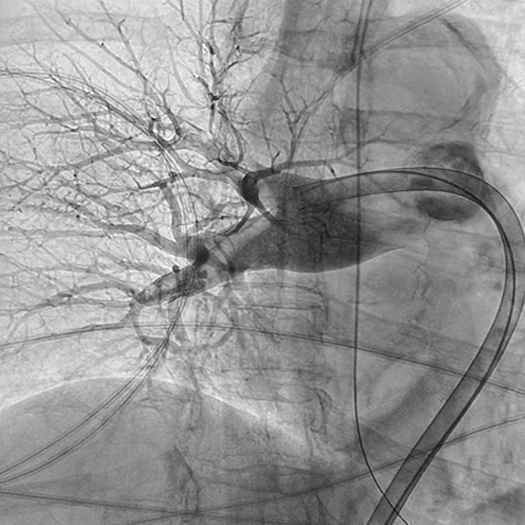

Venous Cases

Images used with permission and provided for illustrative purposes only. Procedural techniques and decisions based on physician’s medical judgment. Individual results may vary. Consents on file at Penumbra, Inc.